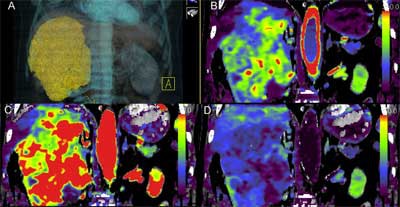

High-frequency volumetric helical perfusion CT imaging potentially has a higher radiation burden than single anatomical-level acquisitions. There has been concern regarding the radiation dose patients could incur from the technique so Dr. Vicky Goh, now the chair of cancer imaging at King's College London, and colleagues sought to determine what the radiation dose was for volumetric helical perfusion CT.

In the study, Goh and colleagues recorded dose-length product (DLP) and CT dose index (CTDIvol) in patients undergoing 4D adaptive spiral CT imaging for tumor evaluation of the thorax, abdomen, and pelvis. The study included 42 consecutive examinations. Mean DLP for the method was 1,288.8 mGy.cm. Mean CTDI was 96.2 mGy. Mean effective dose was 19.6 mSv. In comparison, mean DLP for standard CT staging for the thorax, abdomen, and pelvis was 885.2 mGy.cm. Mean effective dose was 13.3 mSV.